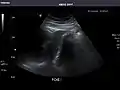

Left kidney

Kidneys: Right and left kidneys measure 11.5 cm and 12 cm in length respectively. No hydronephrosis. Small left lower pole kidney cyst.